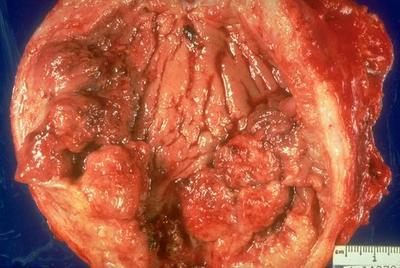

Which of these pictures is pyelonephritis?